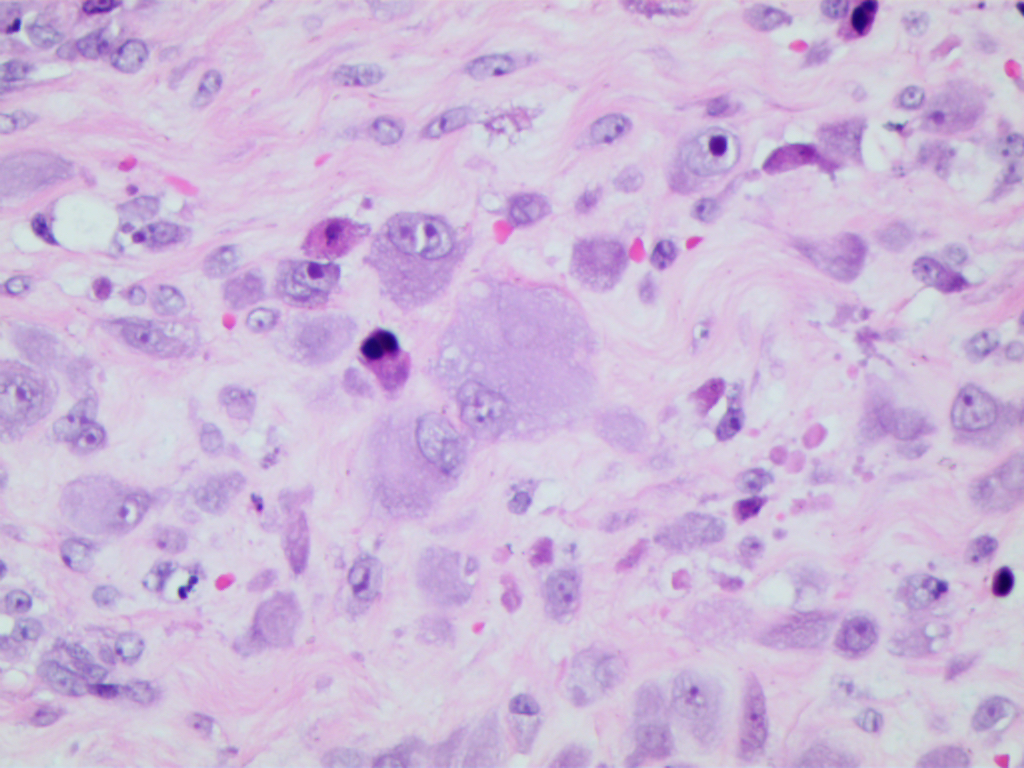

节细胞样细胞体积较大,呈多边形或不规则形,胞质丰富,双染性至嗜碱性,核大,圆形或卵圆形,常偏向胞质一侧,核膜厚,可见 1 ~ 2 个深蓝色散在或成群分布于纤维母细胞或脂肪细胞之间,有些细胞核仁突出,呈紫色包涵体样,致细胞呈核枭眼样;